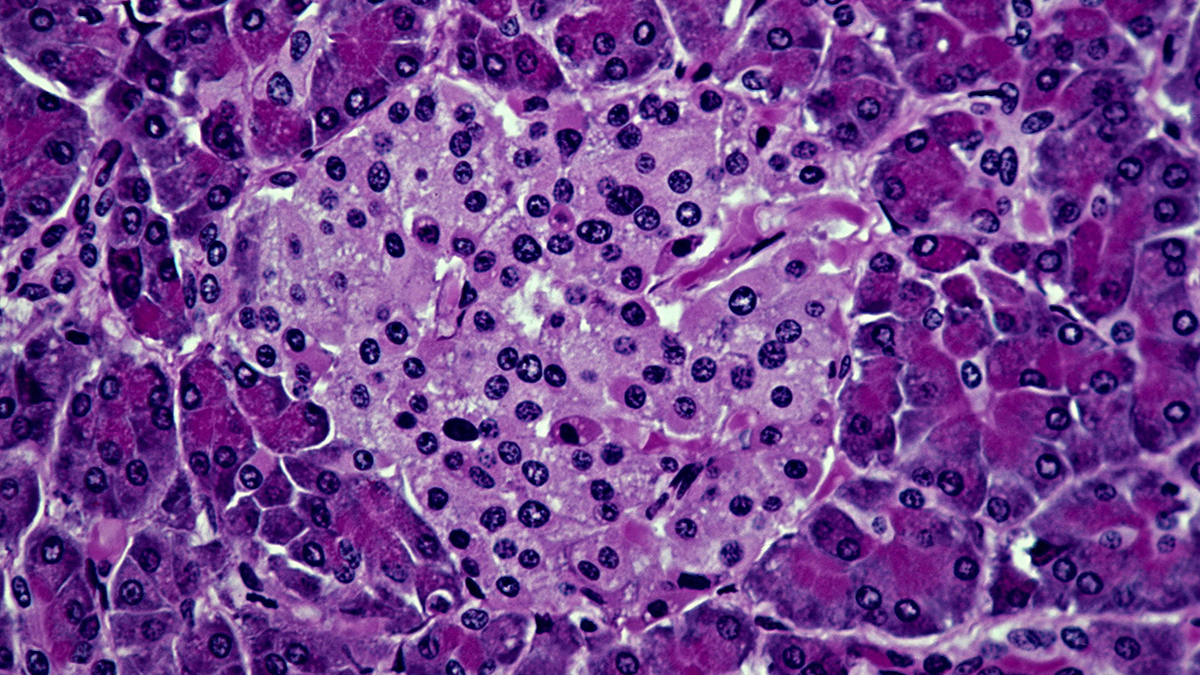

Type 1 diabetes is caused by the body’s own immune system malfuncting, triggering an attack on pancreatic cells called beta islets, which produce insulin. While healthy donor islets can be transplanted into the body, they also risk being attacked, if not completely rejected.